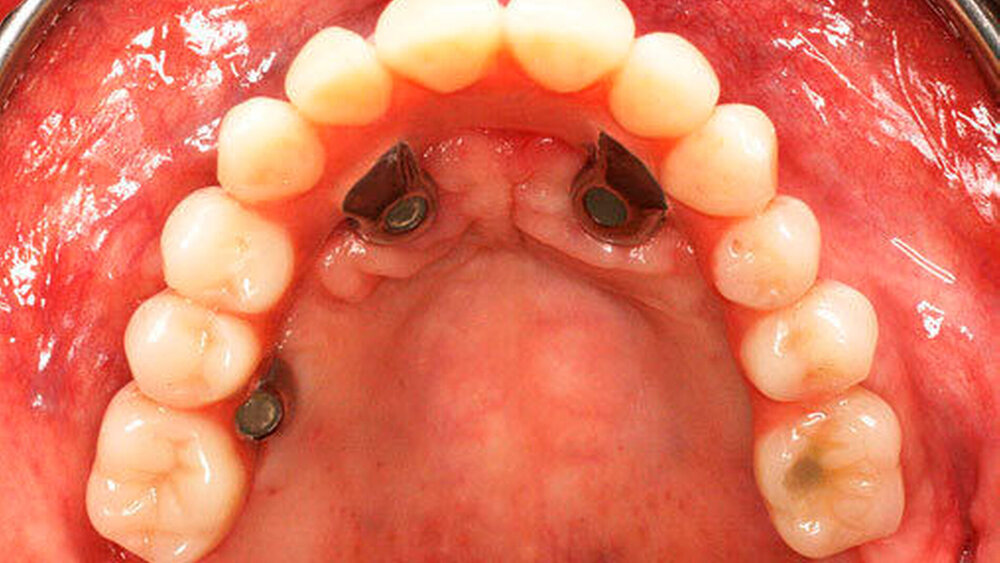

Bei der Sofortversorgung nach dem All-on-4 Konzept (Abbildung 1a-d) werden die frontalen Implantate gerade inseriert und axial belastet, die distalen in der Regel anguliert (Abbildung 2). Durch die Angulation kann ein externer Sinuslift im Oberkiefer umgangen und eine ausreichende Primärstabilisation für eine Sofortversorgung erreicht werden. Im Unterkiefer verhindert das Foramen mentale bei gerader Insertion häufig eine dorsale Positionierung der Implantate. Durch die Angulation der distalen Implantate werden das Belastungspolygon optimiert und ausgeprägte distale Cantilever (Extensionsbrücken) vermieden.

Entscheidend für den Erfolg dieses Konzepts ist die Hygienefähigkeit des Zahnersatzes. Die Basis des Zahnersatzes sollte konvex gestaltet werden und nur linear zum Kieferkamm Kontakt haben (Abbildung 1d). Diese Gestaltung erleichtert eine einfache Mundhygiene mit Interdentalbürsten und Zahnseide. Die Hygienefähigkeit einer All-on-4 Konstruktion ist somit vergleichbar mit einer Stegversorgung. Entscheidend für die Ästhetik ist die präoperative Feststellung der Lippenlachlinie. Diese entscheidet über die Resektionshöhe des Kieferkamms. Die Ästhetik wird bei dieser Versorgungsart ausschließlich über den Zahnersatz erreicht (Abbildung 1d). Die „rote Ästhetik“ kann durch die Verwendung von Prothesenkunststoff individuell und natürlich gestaltet werden. Der Zahnersatz ist bei diesem Konzept okklusal mit den Implantaten verschraubt (Abbildung 1c). Bei Notwendigkeit, zum Beispiel bei Reparaturen, kann dieser durch den Behandelnden leicht ab- genommen werden.